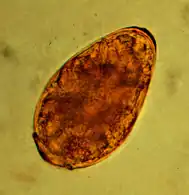

Infection with the kidney worm dioctophyma renale is only found in southern Europe, Asia and North America and is also rare in cats there, the main host being mink. The kidney worm is the largest parasitic nematode with a length of up to one meter and shows a twofold host change: first intermediate hosts are Oligochaeta, second freshwater fish. In the final host it parasitizes mainly in the renal pelvis or fat. Infestation of one kidney usually proceeds without signs of disease. If both kidneys are affected, renal dysfunction may occur as a result of hydronephrosis or pyelonephritis. The infection can be detected by kidney biopsy or imaging techniques. The barrel-shaped, yellow-brown, and 71-84 × 45-52 μm eggs only appear in urine sediment when a female and male kidney worm meet in one kidney.[9]